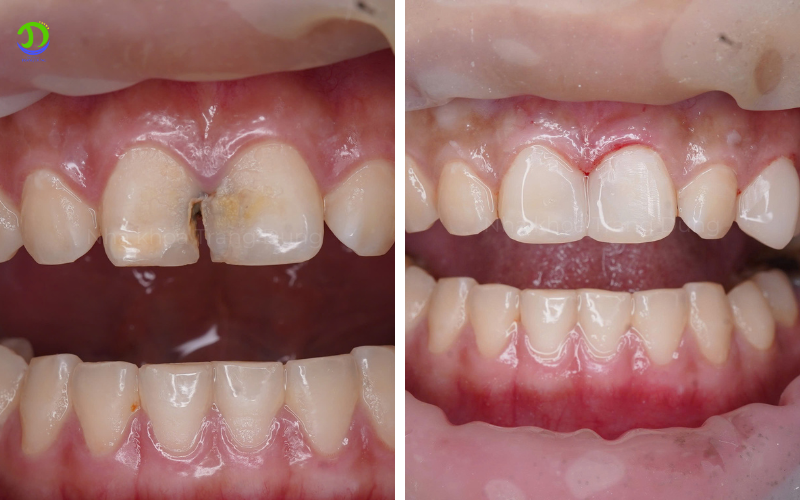

Răng sâu trước và sau khi điều trị tại Nha khoa Trang Dung